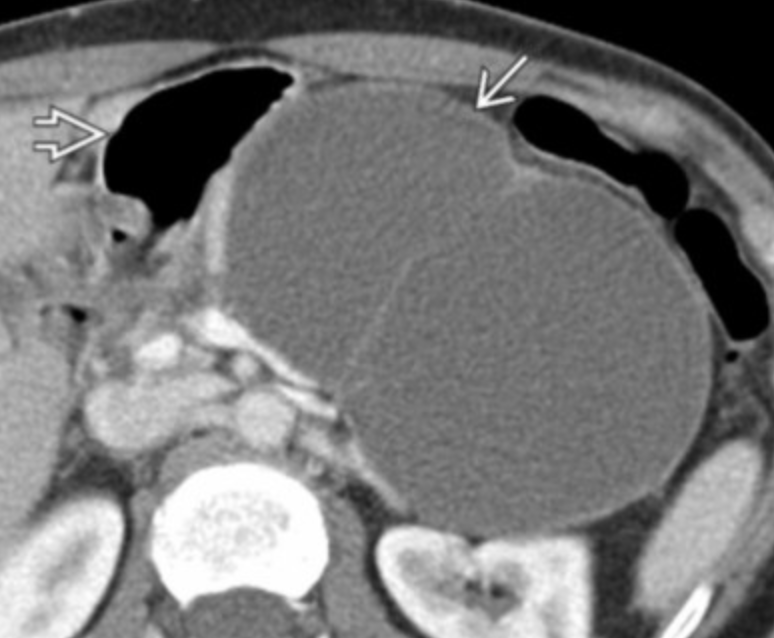

Solid and Pseudopapillary Neoplasma (SPEN)

• Well defined

• Typically in tail of pancreas

• Hypoechoic on US

• Solid mass with hemorrhagic and necrotic focus

• Low risk but still some risk of malignancy

• Women, <35